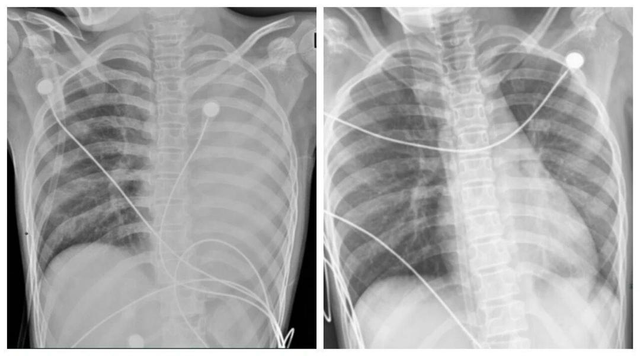

Về mặt y khoa, “phổi trắng” không phải phổi biến đổi màu sắc thật mà là hình ảnh X-quang hoặc CT cho thấy vùng viêm, thâm nhiễm chiếm trên 70% nhu mô phổi. Nếu được điều trị kịp thời bằng kháng virus, kháng sinh, rửa phế quản… phần lớn tổn thương có thể hồi phục.

Tại Việt Nam, số ca cúm đang tăng, trong đó các cơ sở y tế tiếp nhận một số bệnh nhân nặng, bị tổn thương phổi nghiêm trọng, biểu hiện "phổi trắng" qua phim X-quang. Bác sĩ Phạm Văn Phúc, Phó Trưởng khoa Hồi sức tích cực, Bệnh viện Nhiệt đới Trung ương, cho biết đây là dấu hiệu đặc trưng của đợt cúm năm nay.

Tương tự, bác sĩ Trần Quang Thắng, Trưởng khoa Cấp cứu và Đột quỵ, Bệnh viện Lão khoa Trung ương, cho biết đa số cúm thông thường không gây tổn thương phổi. Trong khi đó, dấu hiệu phổi trắng trên phim chụp X-quang thường gặp ở những bệnh nhân nặng, suy hô hấp dẫn đến tổn thương phổi dạng kính mờ hoặc phù phổi cấp. Sau khi hồi phục, bệnh vẫn có thể để lại di chứng nặng nề.

Hình ảnh Xquang phổi của một bệnh nhân bị tổn thương nặng, trắng xóa. Ảnh minh họa: Theo Nature Publishing

Ngoài ra, tổn thương do virus tạo điều kiện cho vi khuẩn dễ dàng xâm nhập, gây bội nhiễm phổi và làm tình trạng viêm trở nên nghiêm trọng hơn. Hậu quả cuối cùng là tổn thương phổi cấp tính (ARDS), khi các phế nang bị lấp đầy bởi dịch viêm, protein huyết tương và màng hyalin, dẫn đến suy hô hấp trầm trọng và hình ảnh trắng đục lan tỏa trên X - quang hoặc CT phổi.